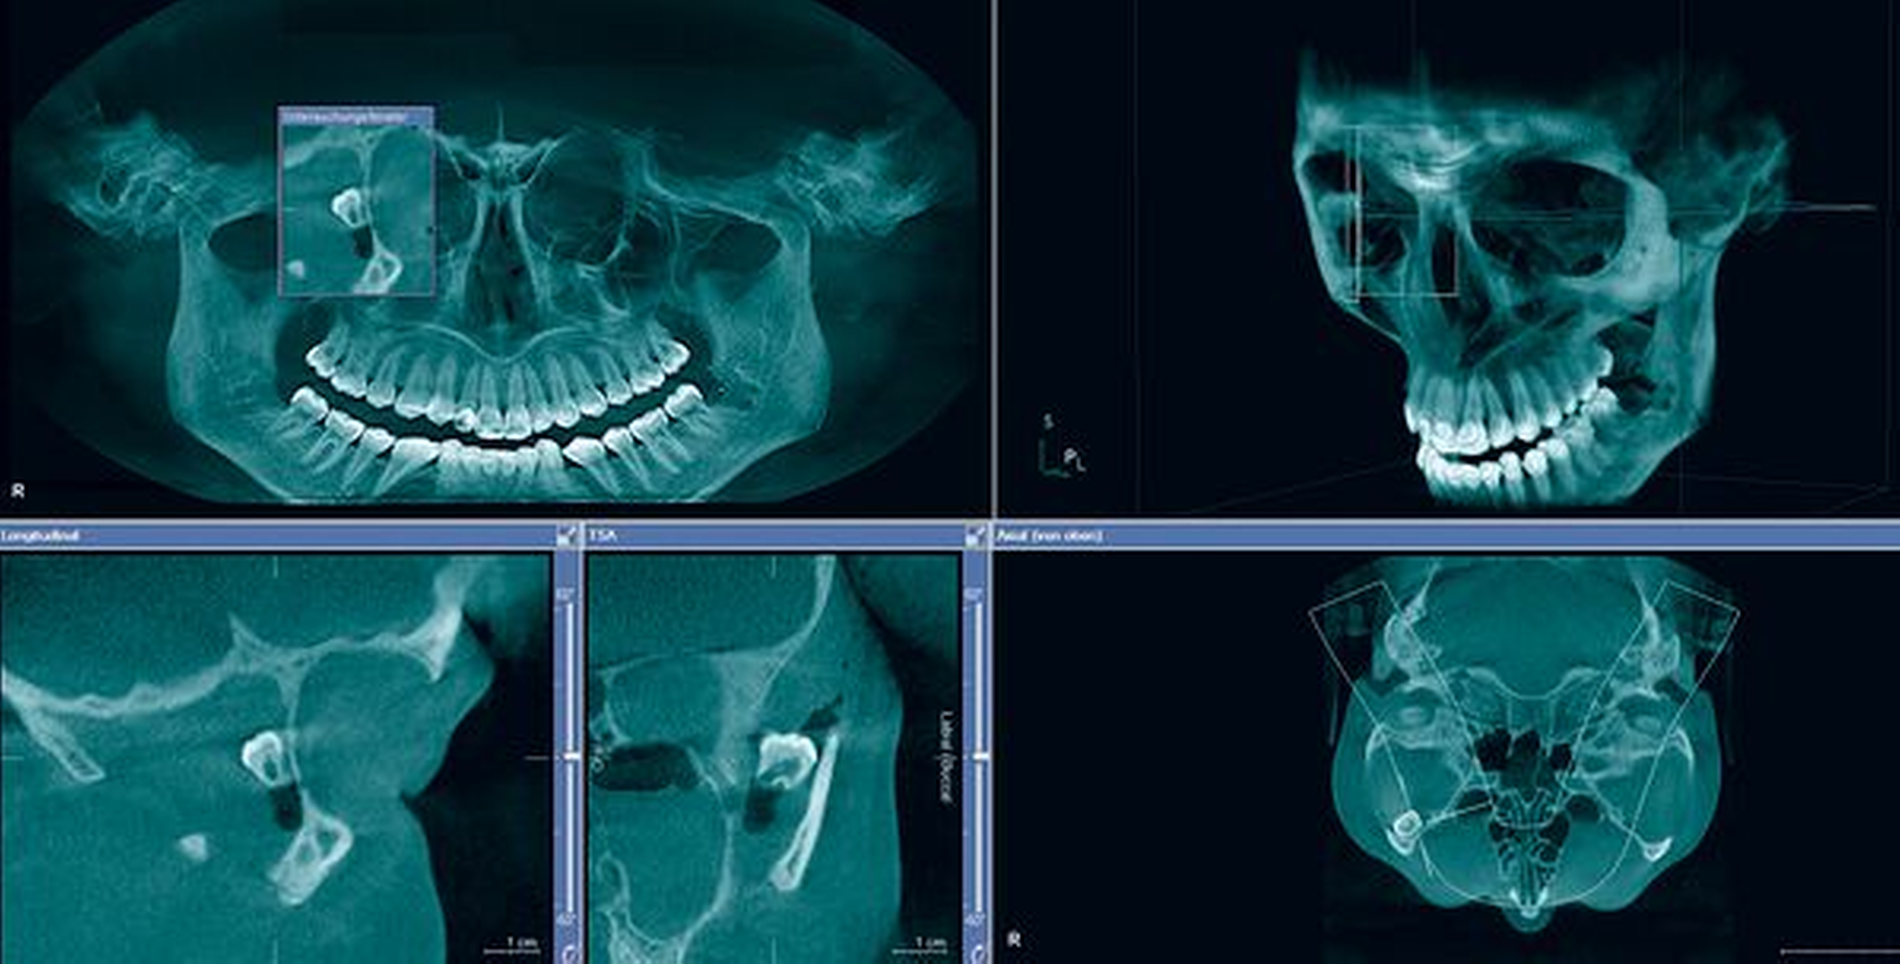

Bei der Vorstellung erfolgte eine dreidimensionale radiologische Diagnostik mittels Digitaler Volumentomografie (DVT). Die Befundung ergab, dass der Weisheitszahn 18 in die Fossa temporalis luxiert worden war. Das umliegende Gewebe wies ein deutliches Emphysem auf, das durch den frustranen Versuch des Vorbehandlers, den Zahn durch den enoralen Zugang zu entfernen, zustande gekommen war. Aufgrund der starken Gesichtsschwellung und der eingeschränkten Mundöffnung konnte keine intraorale Begutachtung der Wundsituation erfolgen.

In Intubationsnarkose konnte über einen blepharoplastischen Oberlidzugang zunächst die Fossa temporalis dargestellt werden. Der Vorteil eines Oberlidzugangs besteht in der Möglichkeit, den Zugangsweg in der natürlichen Oberlidfalte zu setzen, so dass im ästhetischen Bereich keine Narben sichtbar sind. Der in der DVT vermutete Weisheitszahn zeigte sich nach mehrschichtiger Präparation des Weichgewebes schließlich lateral der Orbita und kranial des Jochbogens. Somit konnte der dislozierte Weisheitszahn nach aufwendiger Darstellung und Schonung der umliegenden Gewebe vollständig entfernt werden.

Im vorliegenden Patientenfall wurde der Weisheitszahn 18 entsprechend der Anatomie nicht orthograd durch den enoralen Zugangsweg entfernt, sondern über einen Zugangsweg zur Fossa temporalis über das Oberlid der Patientin. Eine Luxation des Weisheitszahnes durch die Fissura pterygomaxillaris hat vermutlich dazu geführt, dass der Zahn weiter mobilisiert wurde und schließlich an der postolateralen Fläche der Maxilla in die Fossa temporalis bewegt wurde. Der Zahn kam dann schlussendlich lateral der Orbita in einer Position zu liegen, die nicht mehr durch einen enoralen Zugang erreicht werden konnte.